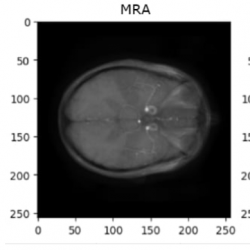

IXI dataset: Upon reviewing and analysing the entire IXI dataset, it was observed that there are 2 contrasts that exist in different templates from the remaining. The middle original slices of the 4 contrasts are shown in Fig.

10:

Fig. 10

Illustration of axial slices of IXI dataset before registration.

As depicted in Fig.

10, it is evident that MRA images are in shapes (512, 512, 100), while T1 images are in completely different templates (size and plane). However, it is noteworthy that there are still PD and T2 images in the same template and similar to BraTS2020 images. In light of this observation, the decision is made to apply some registering transformations to MRA and T1 images using the common template synthesized from PD and T2. For this experiment, an affine transformation is employed from the AntsPy package (Avants